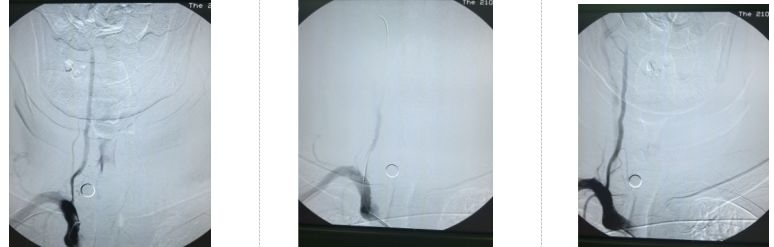

图4.右椎动脉支架成形术

图5.左侧颈内动脉支架成形术

术后为预防高灌注损伤,积极控制血压在110/70mmHg水平,并给予依达拉奉注射液清除自由基,继续双抗、他汀降脂及内科治疗,患者病情平稳,未出现新发神经系统症状及体征。术后次日,复查头颅CT示颅内未见出血及高灌注表现。患者血压逐渐调整至130/80mmHg水平,病情稳定,右侧肢体无力、麻木缓解,术后第3日顺利出院。

图6.术后次日头颅CT示颅内未见出血